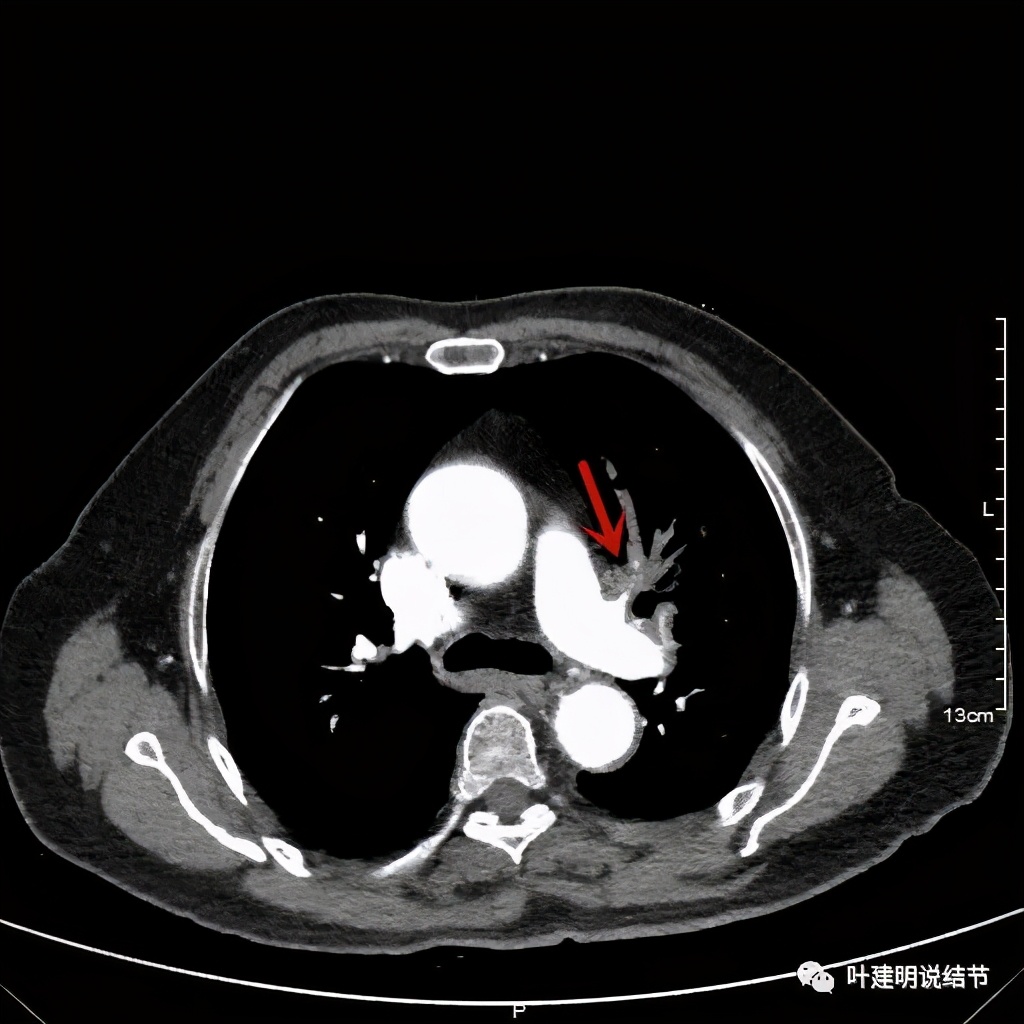

上图示肿瘤部位仍与肺动脉关系密切,似乎未能脱开,红色示肿瘤处